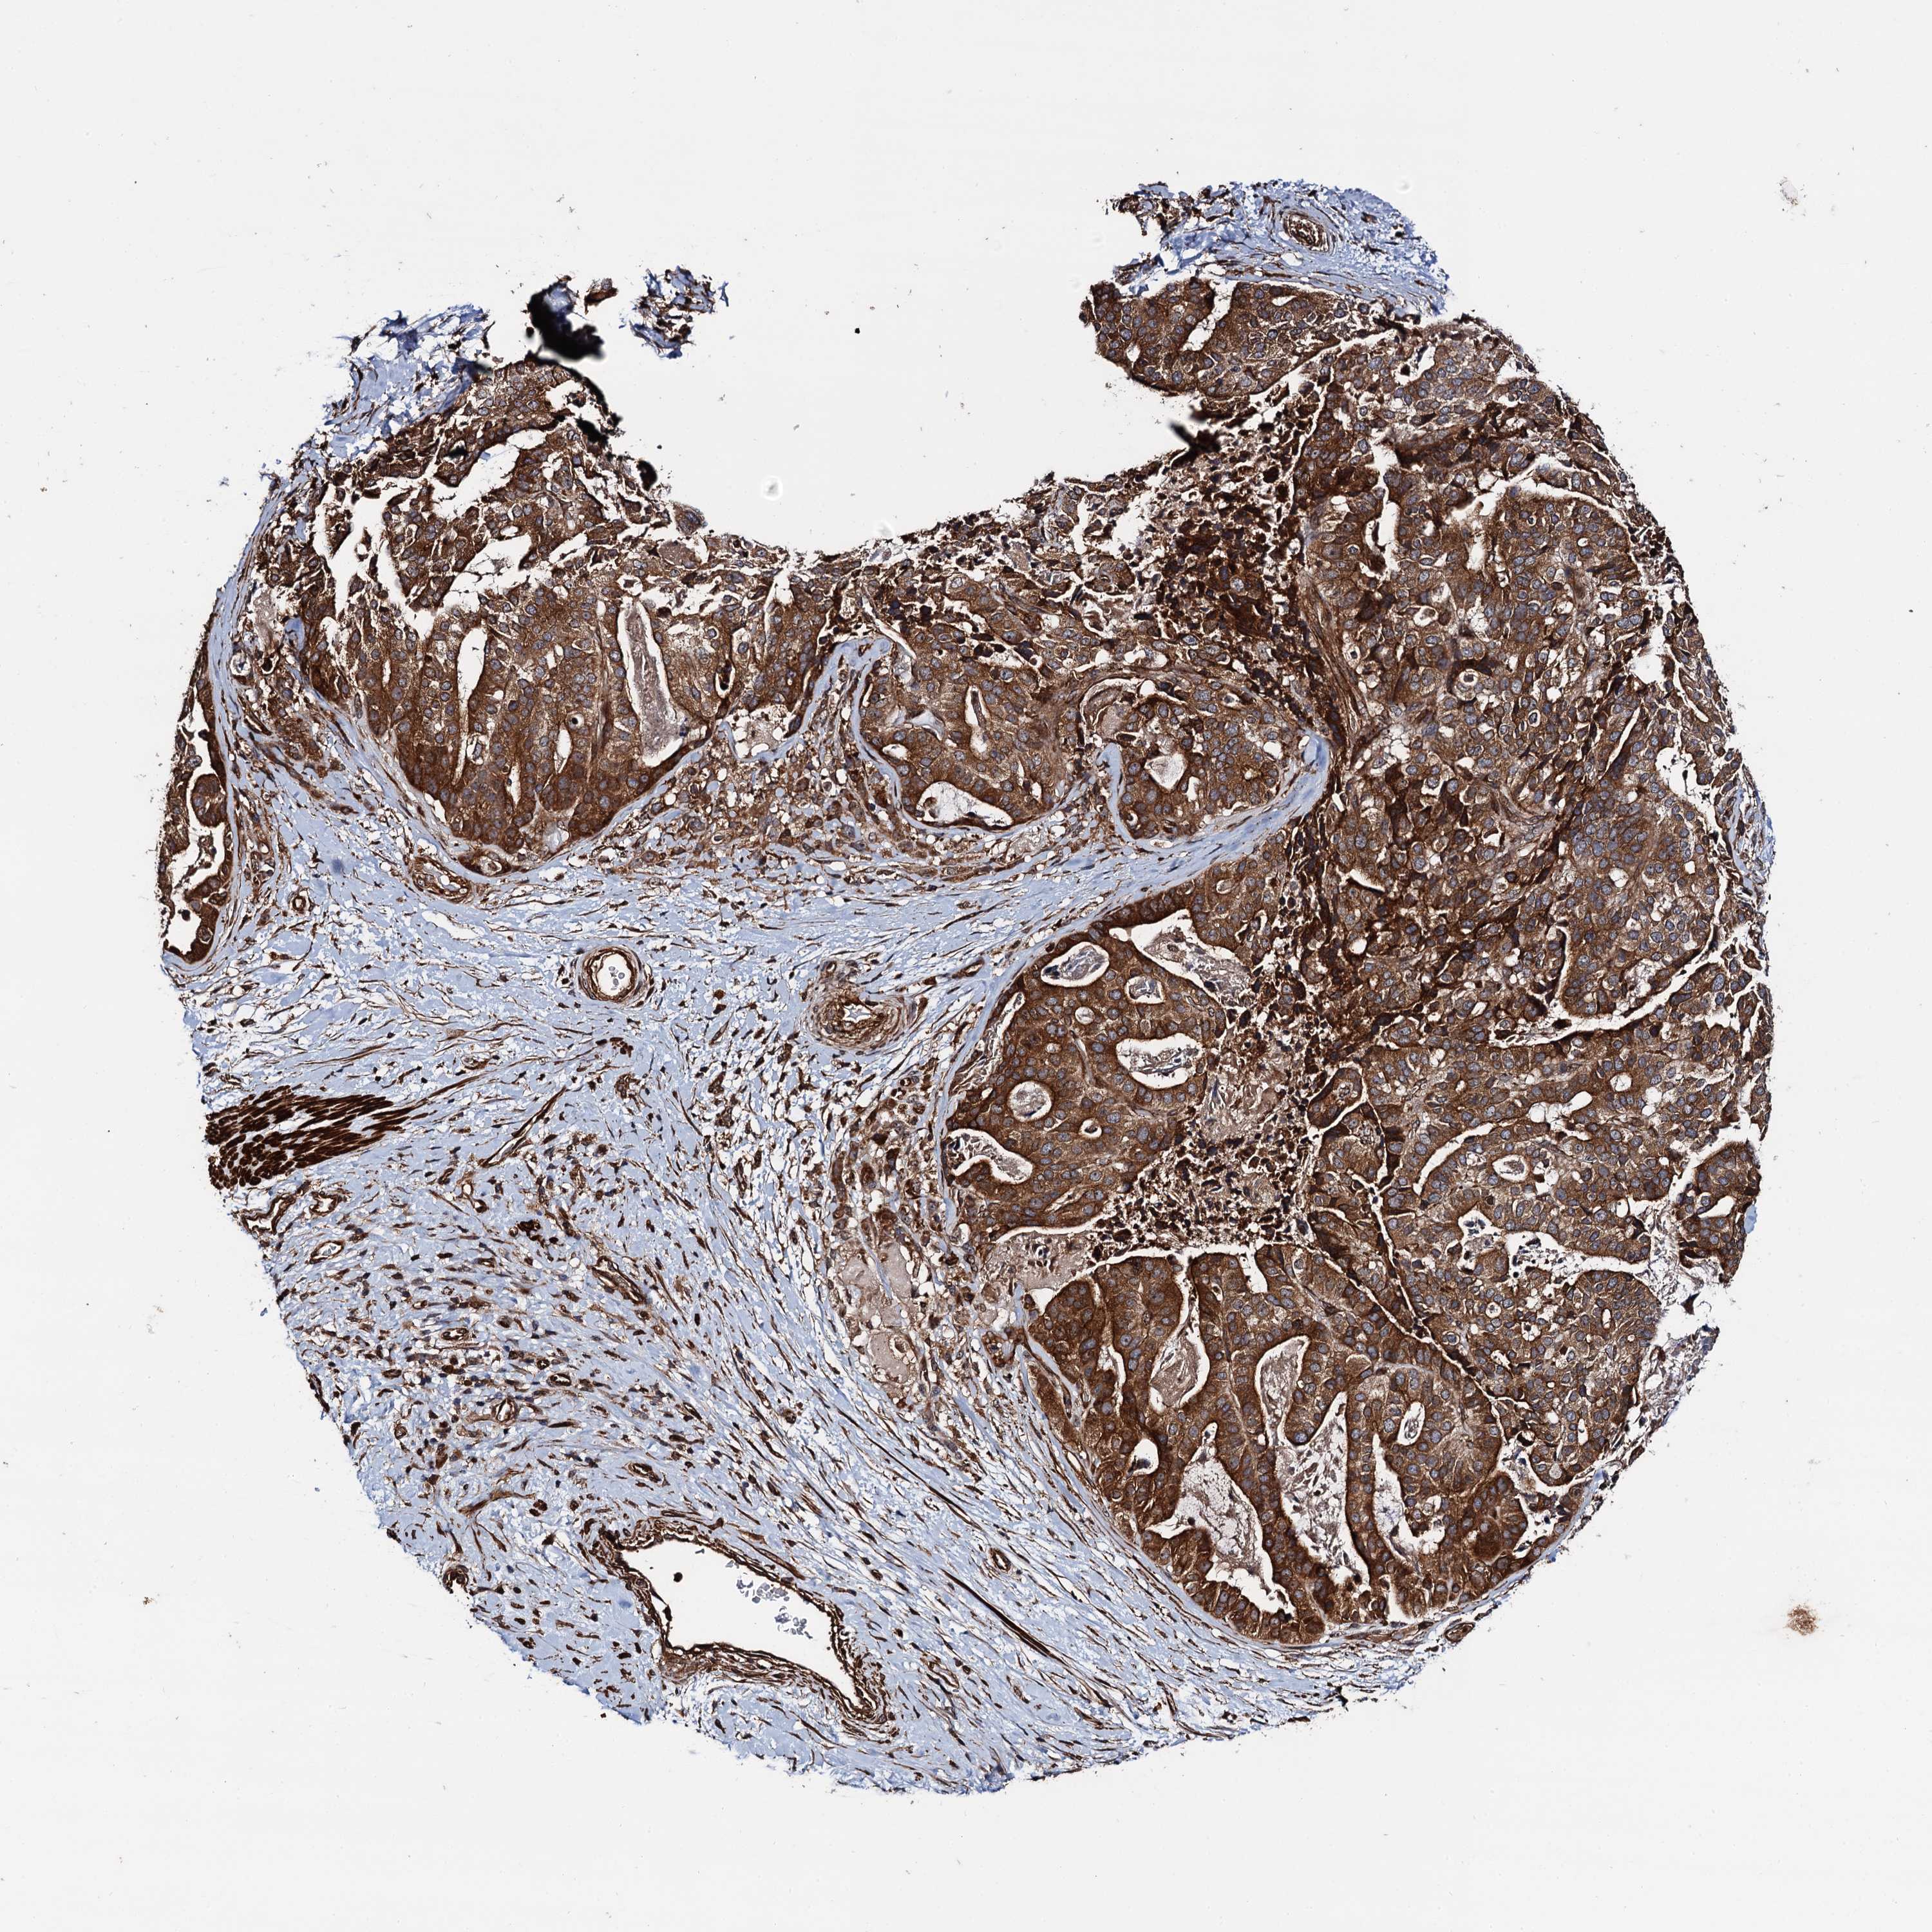

STOMACH CANCER - Protein expressioni

A mouse-over function shows sample information and annotation data. Click on an image to view it in a full screen mode. Samples can be filtered based on level of antibody staining by selecting one or several of the following categories: high, medium, low and not detected. The assay and annotation is described here.

Note that samples used for immunohistochemistry by the Human Protein Atlas do not correspond to samples in the TCGA dataset.

Antibody stainingi

Antibody staining in the annotated cell types in the current human tissue is reported as not detected, low, medium, or high, based on conventional immunohistochemistry profiling in selected tissues. This score is based on the combination of the staining intensity and fraction of stained cells.

Each image is clickable and will lead to virtual microscopy that enables deeper exploration of all samples and also displays staining intensity scores, fraction scores and subcellular localization as well as patient and tissue information for each sample.

Antibody HPA040866

Staining

High

Medium

Low

Not detected

Intensity

Strong

Moderate

Weak

Negative

Quantity

>75%

75%-25%

<25%

None

Location

Nuclear

Cytoplasmic/membranous

Cytoplasmic/membranous,nuclear

Adenocarcinoma, NOS

Adenocarcinoma, High grade